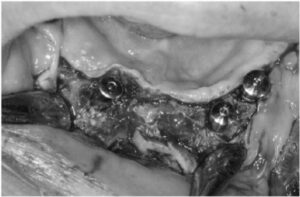

아래턱 잔존 치아 발치 후

한 달 반 정도 지났을 때

충분한 뼈이식을 동반한

임플란트 식립을 진행하였는데요.

상실된 치아의 개수에 맞게

식립을 하면 가장 좋겠지만

처음 내원 당시 잇몸뼈 상태가

많이 좋지 않았었기 때문에

안정적으로 식립이 가능한 위치를 선정하여

식립을 도와드렸으며,

고정형 스크류를 통해

이식한 뼈가 단단히 자리 잡을 수 있도록

고정해 주었습니다.